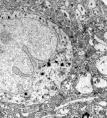

Nectome 正在研究如何保存人脑从而维持神经元间的连接。有人推测这样的“连接组”(connectome)能够保持个体的记忆信息。该公司已经获得联邦政府拨款,达成了与 麻省理工学院顶级神经科学家 Edward Boyden 的合作。此外,Nectome 的技术因成功保存了一只猪脑而赢得了价值 8 万美金的科学奖,由于大脑保存得极其完好,以至于每一个突触在电镜下都清晰可见。

图丨保存的猪脑在电镜下可见层叠的细胞和突触。有人相信作出这样一幅“连接组”图谱能帮助重构记忆。